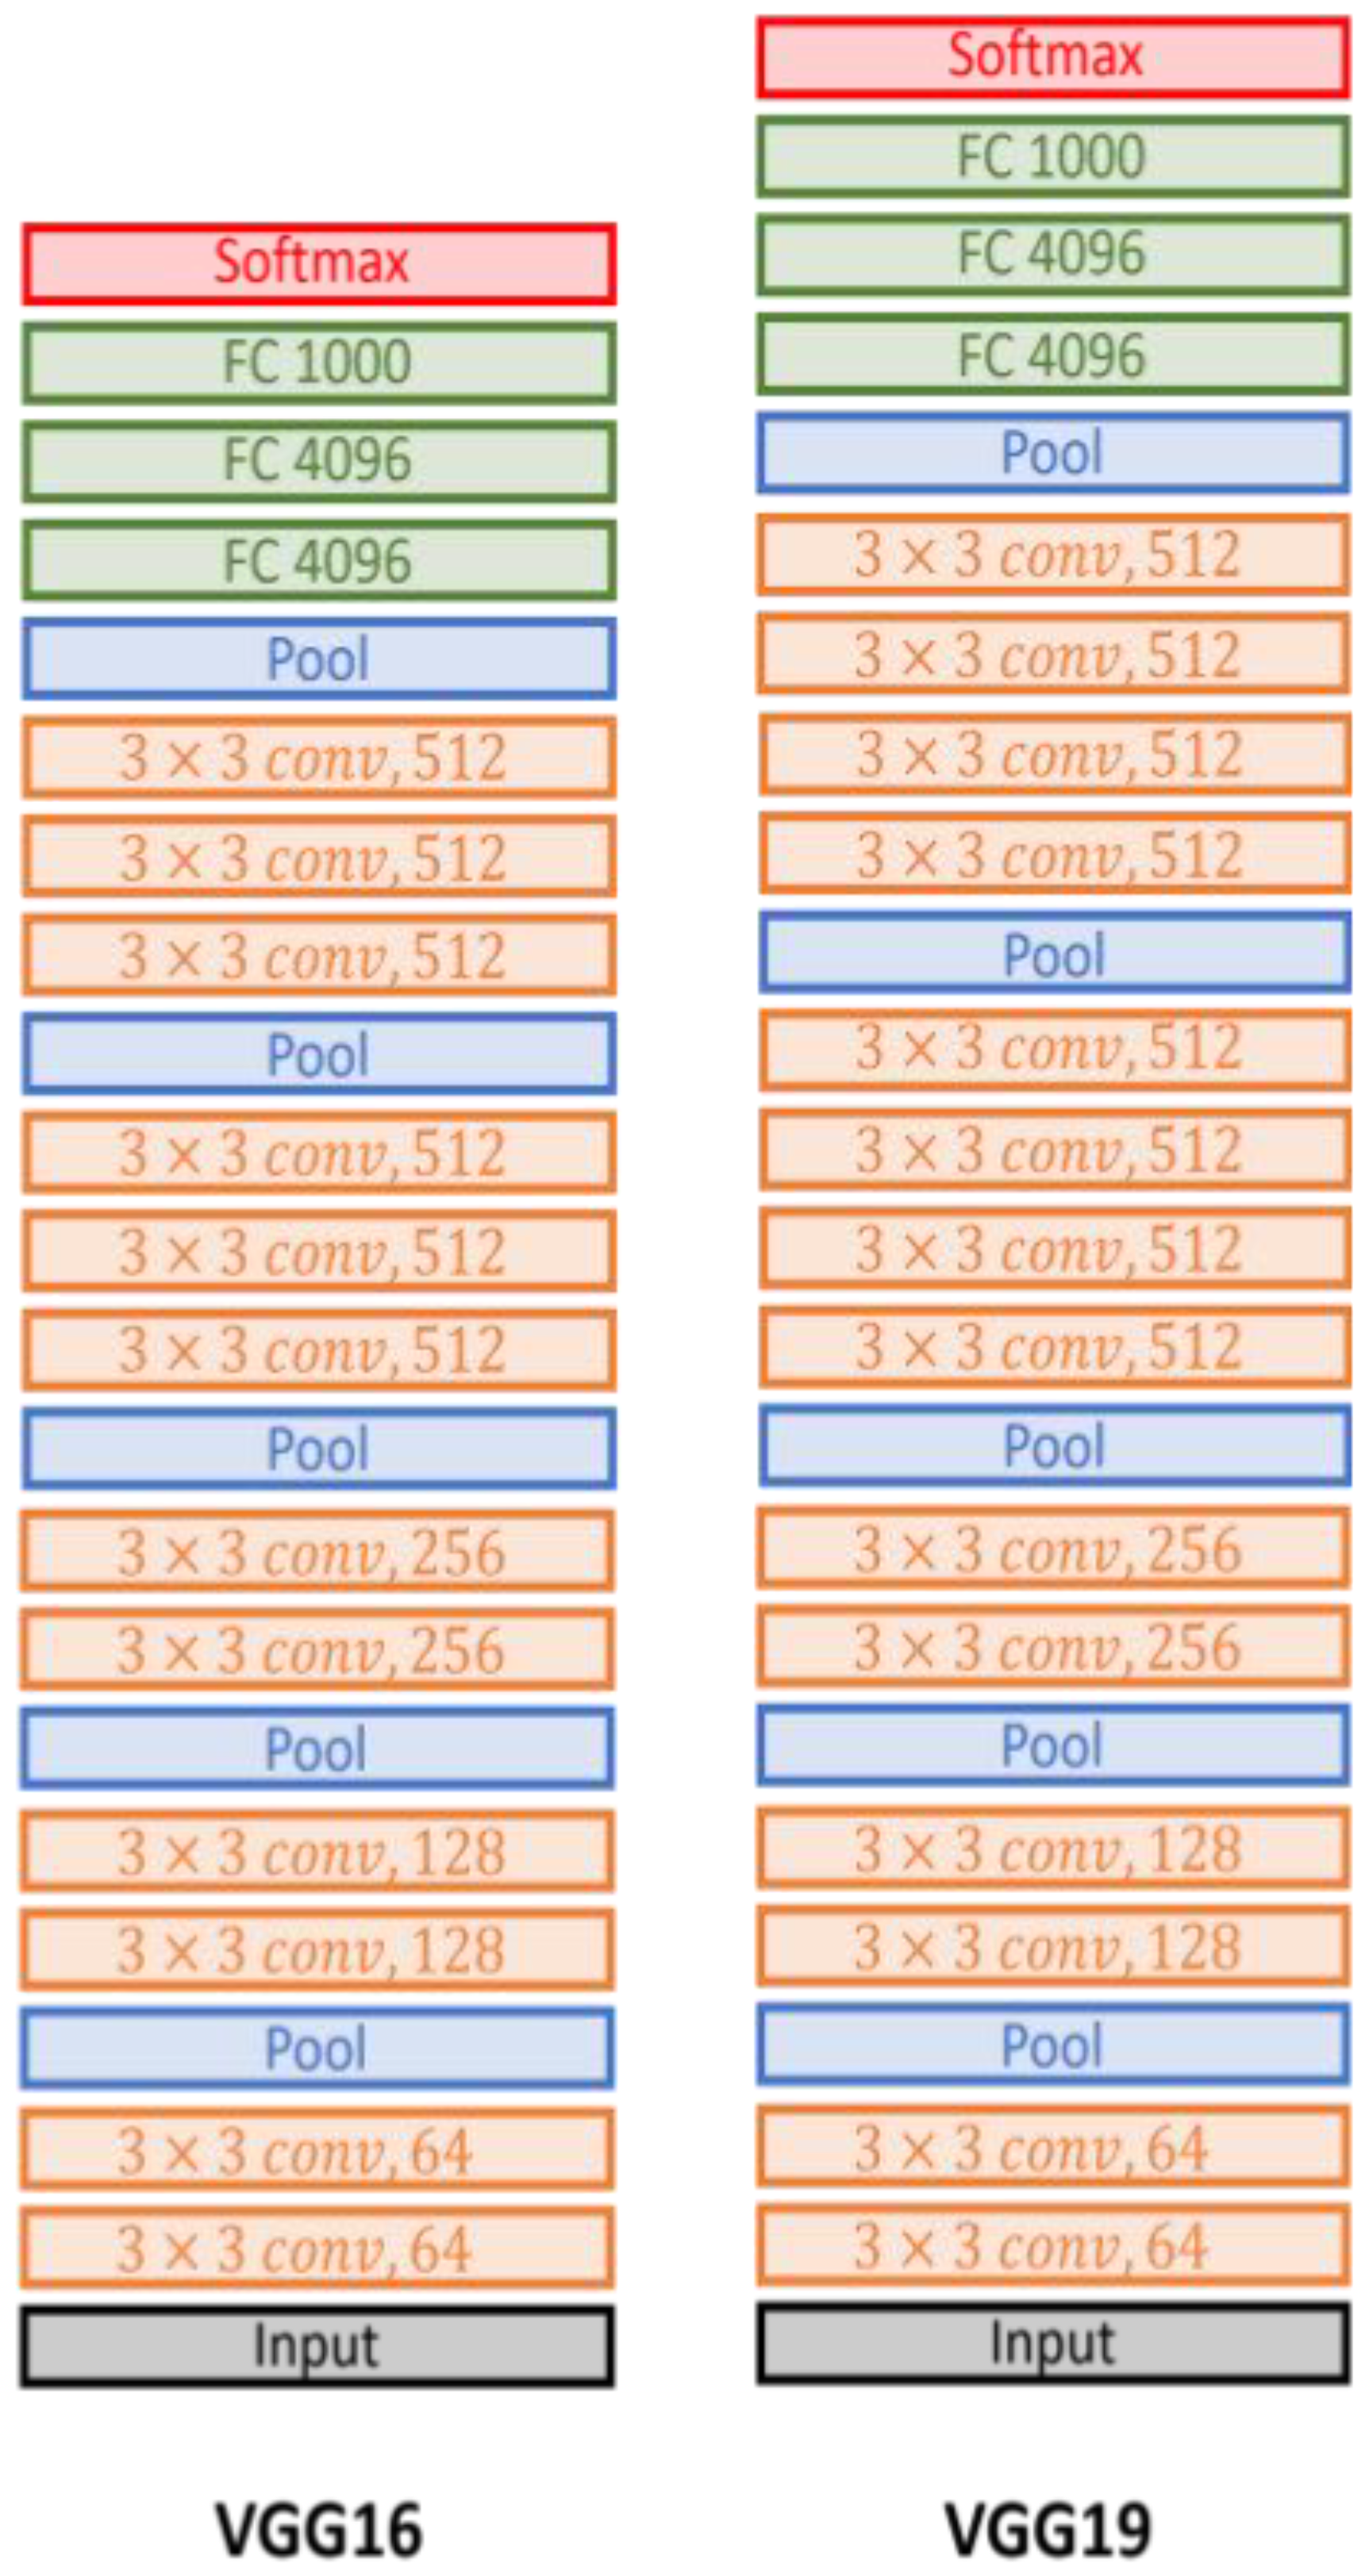

- VGG-19